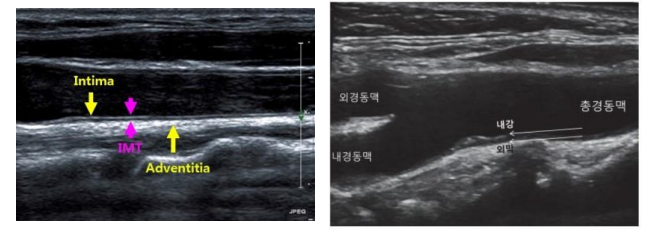

좌측:심장칼슘CT/우측:경동맥초음파

- 경동맥 초음파는 어떤 검사입니까?경동맥 에코는 심장에서 머리로 올라가는 동맥을 직접 초음파로 관찰하게 되는 것입니다.

심장에서 머리로 올라가는 동맥을 초음파로 보는 검사입니다① 혈관벽(Intima-mediathickness(IMT) 두께가 0.9mm이상으로 두꺼우거나 정상치의 75th percentile 이상이면 이상으로 간주합니다.② 혈관의 혈전(plaque)이 최근 혈관벽의 두께보다 더 중요한 의미를 가지는데 주변벽보다 50% 이상 두껍거나 1.5mm 이상 혈관벽의 두께를 나타내면 plaque가 있는 것으로 보입니다. 두께도 중요하지만 떨어져 가면 뇌졸중이기 때문에 혈전이 어떤 형태인지도 중요합니다.③ 혈관이 70% 이상 좁아진 경우에는 혈관 시술을 고려해야 합니다. stent를 넣거나…

- Plaque definition 1) focal wall thickening that is ≧ 50% greater than the surrounding vessel wall, 2) Focal region with an the surrounding vessel wall, 2) Focal region with an IMT

- * Plaque assessment 1) Plaque echogenicity, texture-homogeneous, heterogeneous-calcified, iso-echoic, hypo-echoic2) Doppler sonogra